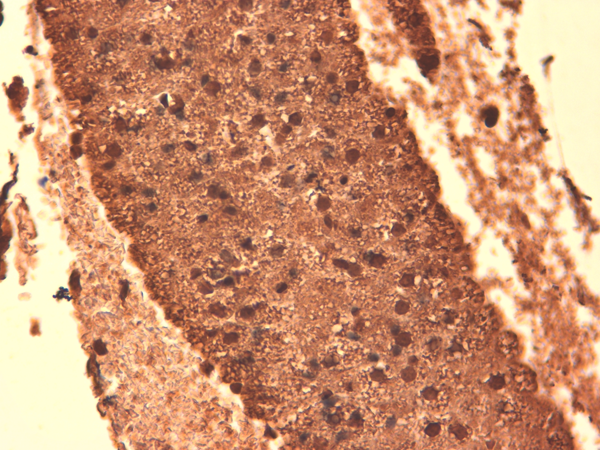

IHC (Immunohistochemistry)

(Immunohistochemistry analysis using Mouse Anti-Sodium Iodide Symporter Monoclonal Antibody, Clone 14F. Tissue: Thyroid. Species: Mouse. Fixation: 10% Formalin Solution for 12-24 hours at RT. Primary Antibody: Mouse Anti-Sodium Iodide Symporter Monoclonal Antibody at 1:1000 for 1 hour at RT. Secondary Antibody: HRP/DAB Detection System: Biotinylated Goat Anti-Mouse, Streptavidin Peroxidase, DAB Chromogen (brown) for 30 minutes at RT. Counterstain: Mayer Hematoxylin (purple/blue) nuclear stain at 250-500 ul for 5 minutes at RT.)